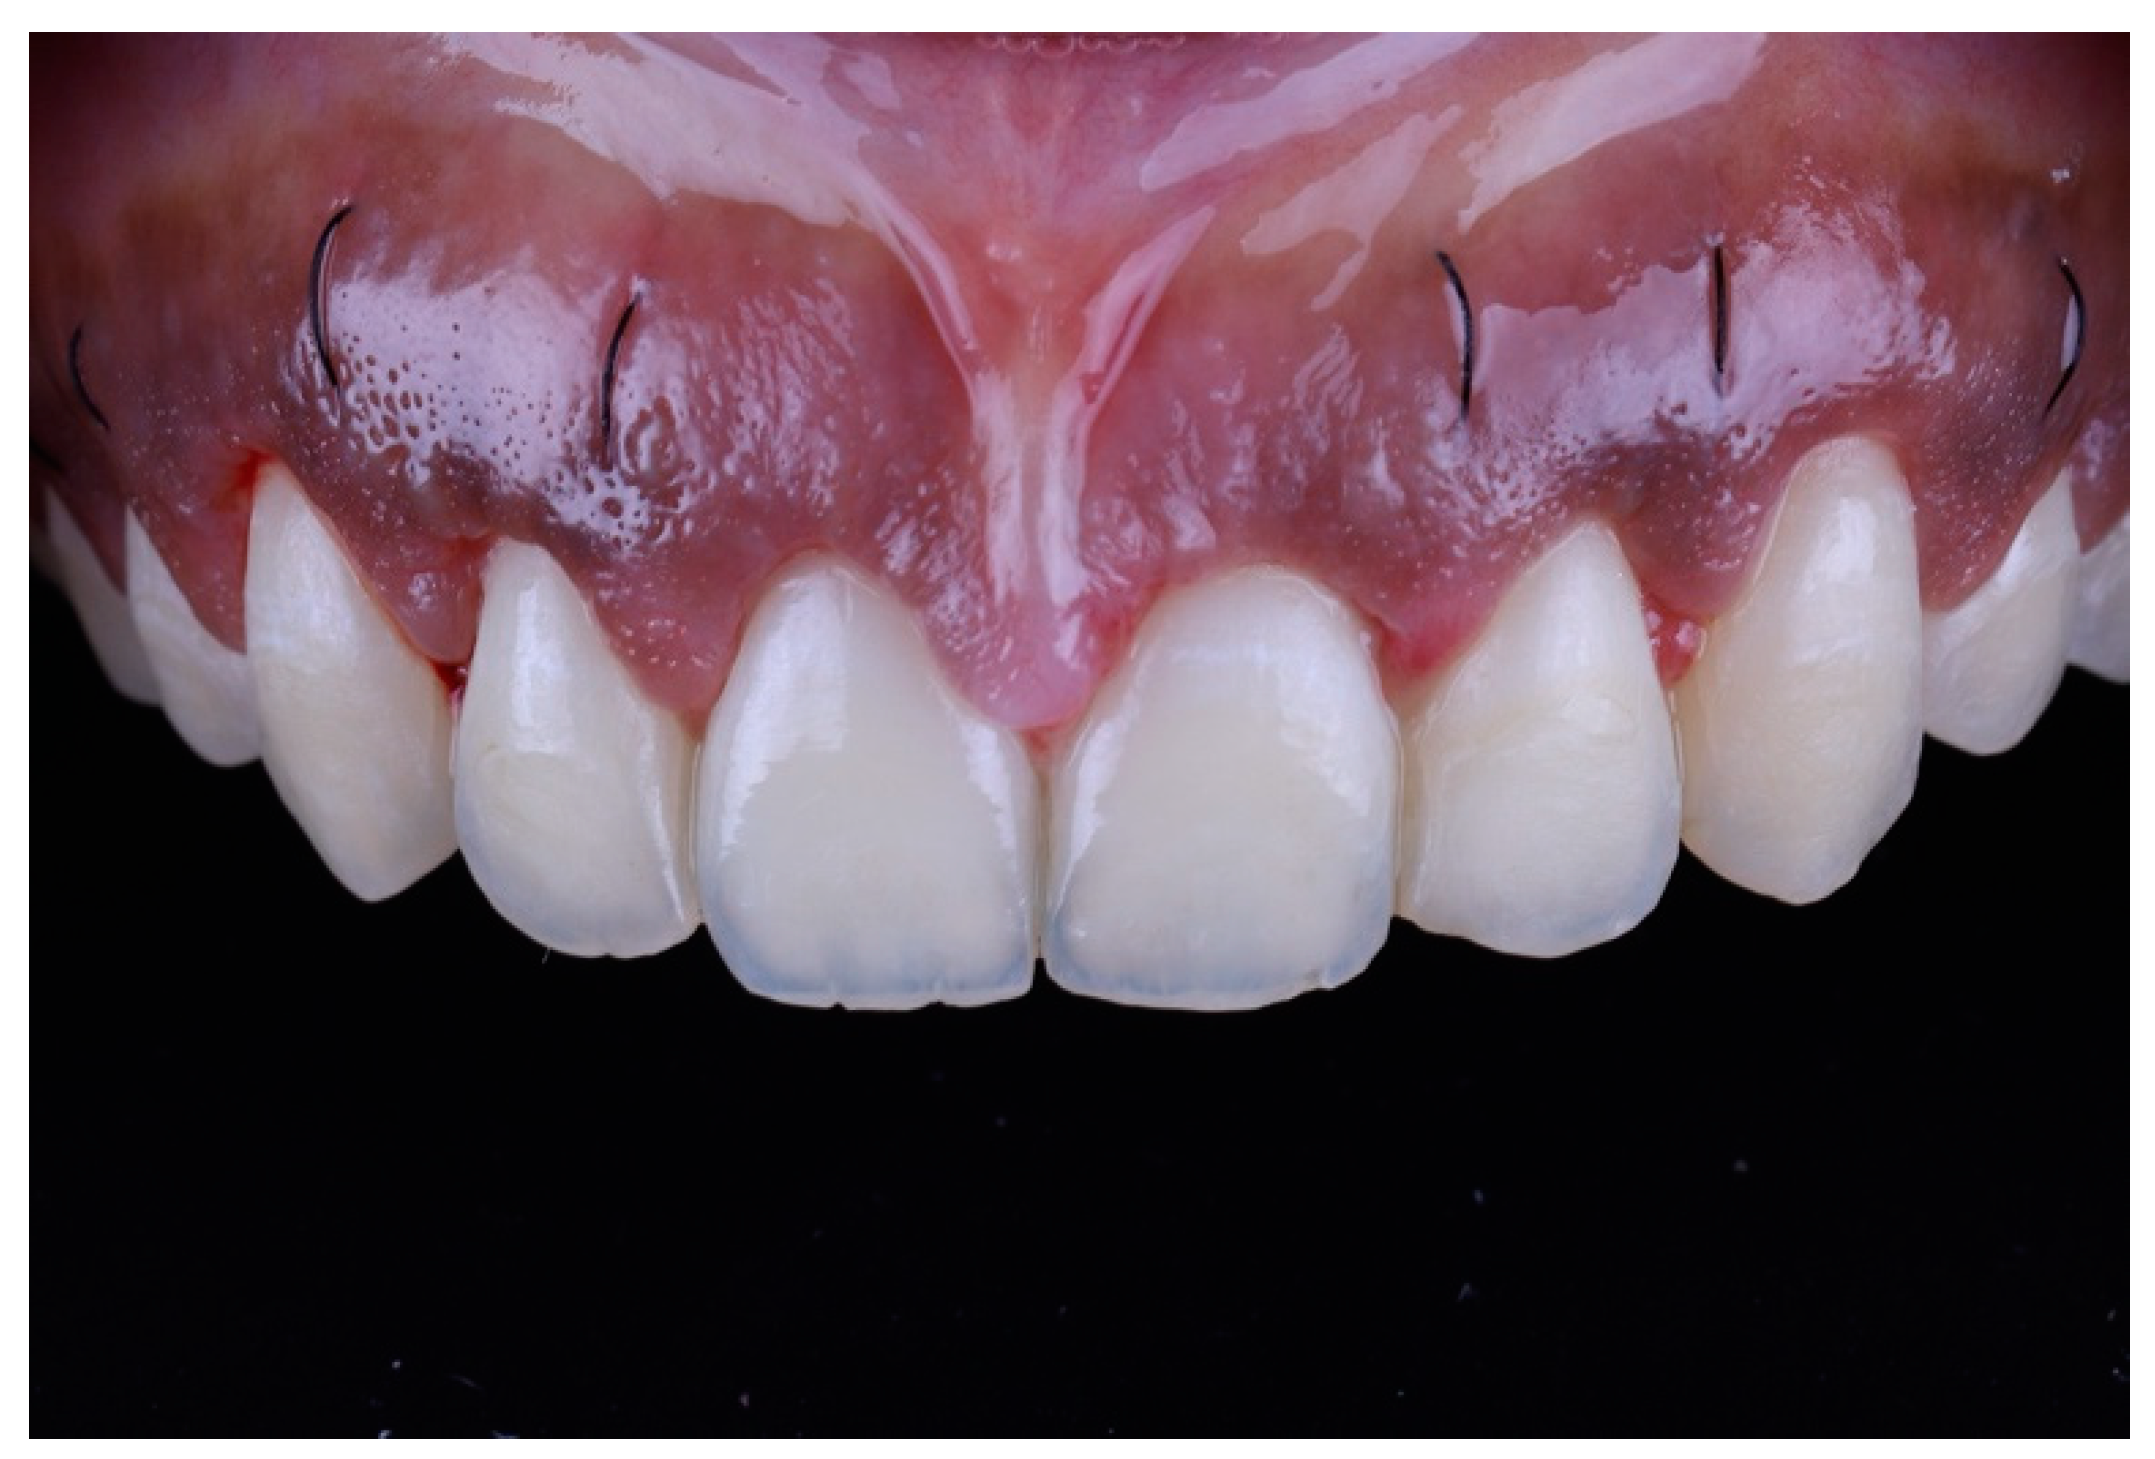

A full thickness mucoperiosteal flap was elevated past the mucogingival junction (Figure 7). The surgical guide was then placed again to determine the extent of osteoectomy needed (Figure 8), and the bone was marked with a round carbide bur. Using an end cutting carbide bur, osteoectomy was then performed; osteoplasty was performed after to remove buccal bone buttressing (Figure 9). The guide was then placed for a final check before internal vertical mattress sutures were placed using a monofilament non-resorbable material (5.0 Prolyne, Ethicon Inc, Somerville, NJ, USA) and hemostasis was ensured.

Figure 7.

Mucoperiosteal flap elevated.

Figure 8.

Surgical guide placed to determine level of osteoectomy.

After surgery, the patient was instructed to take 600 mg ibuprofen 3 times/day for the first 7 days and to rinse with 0.12% chlorhexidine gluconate twice daily. On the 10th post-operative day, the patient presented for suture removal. Healing was uneventful (Figure 10). The patient then presented for recall at 6 weeks, and showed satisfactory outcomes at the 6 month follow-up (Figure 11 and Figure 12).

Figure 10.

At 10-day follow up.